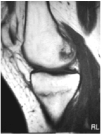

Ante los hallazgos se solicitó una resonancia nuclear magnética de la rodilla izquierda, que informó de focos de contusión ósea con fractura trabecular en vertiente medial interna de la tibia y edema intraóseo asociado (figs. 1 y 2); meniscos y ligamentos íntegros en todas las secuencias, articulación congruente y partes blandas sin hallazgos (figs. 3, 4 y 5).

Fig. 1.--RMN de rodilla izquierda. Corte sagital potenciado en T1.

Fig. 2.--RMN de rodilla izquierda. Corte sagital potenciado en T2.